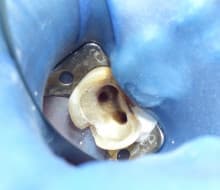

精密根管治療(マイクロエンド)